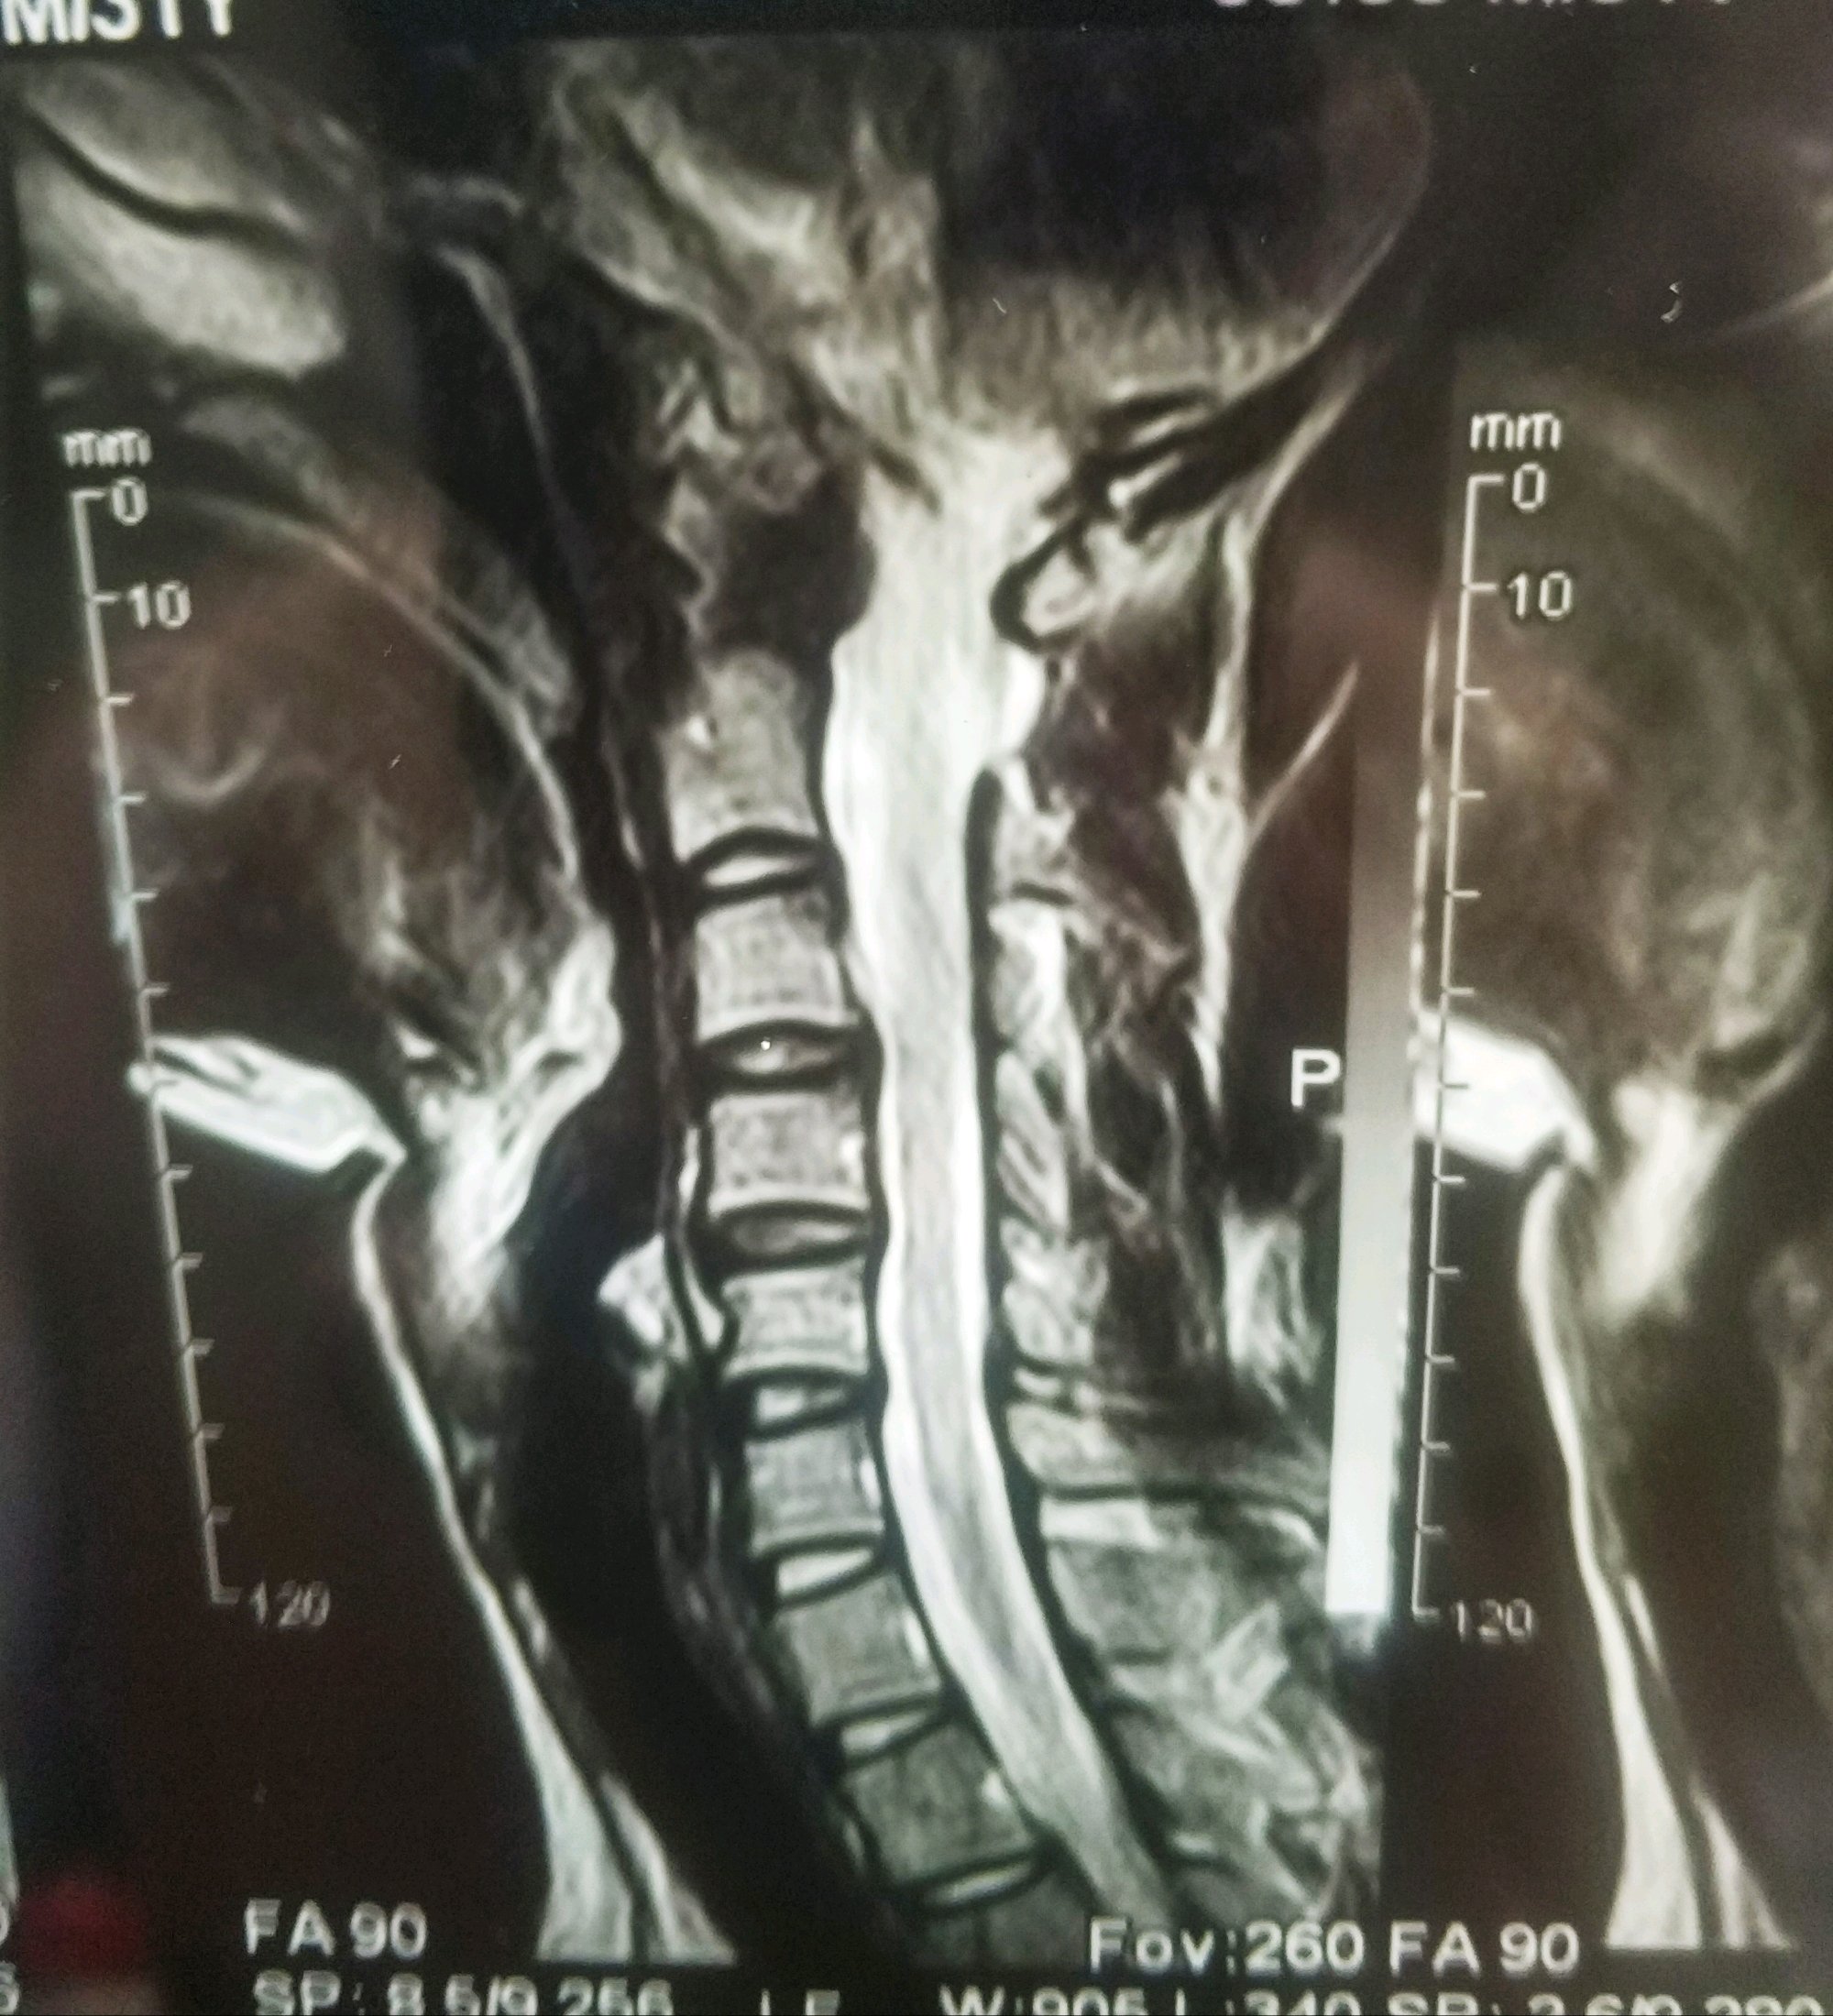

哪位哥哥姐姐们帮忙看看,这个要怎么锻炼,医生说断断续续不给治

哪位哥哥姐姐们帮忙看看,这个要怎么锻炼,医生说断断续续不给治,让我请假。确实没时间啊,